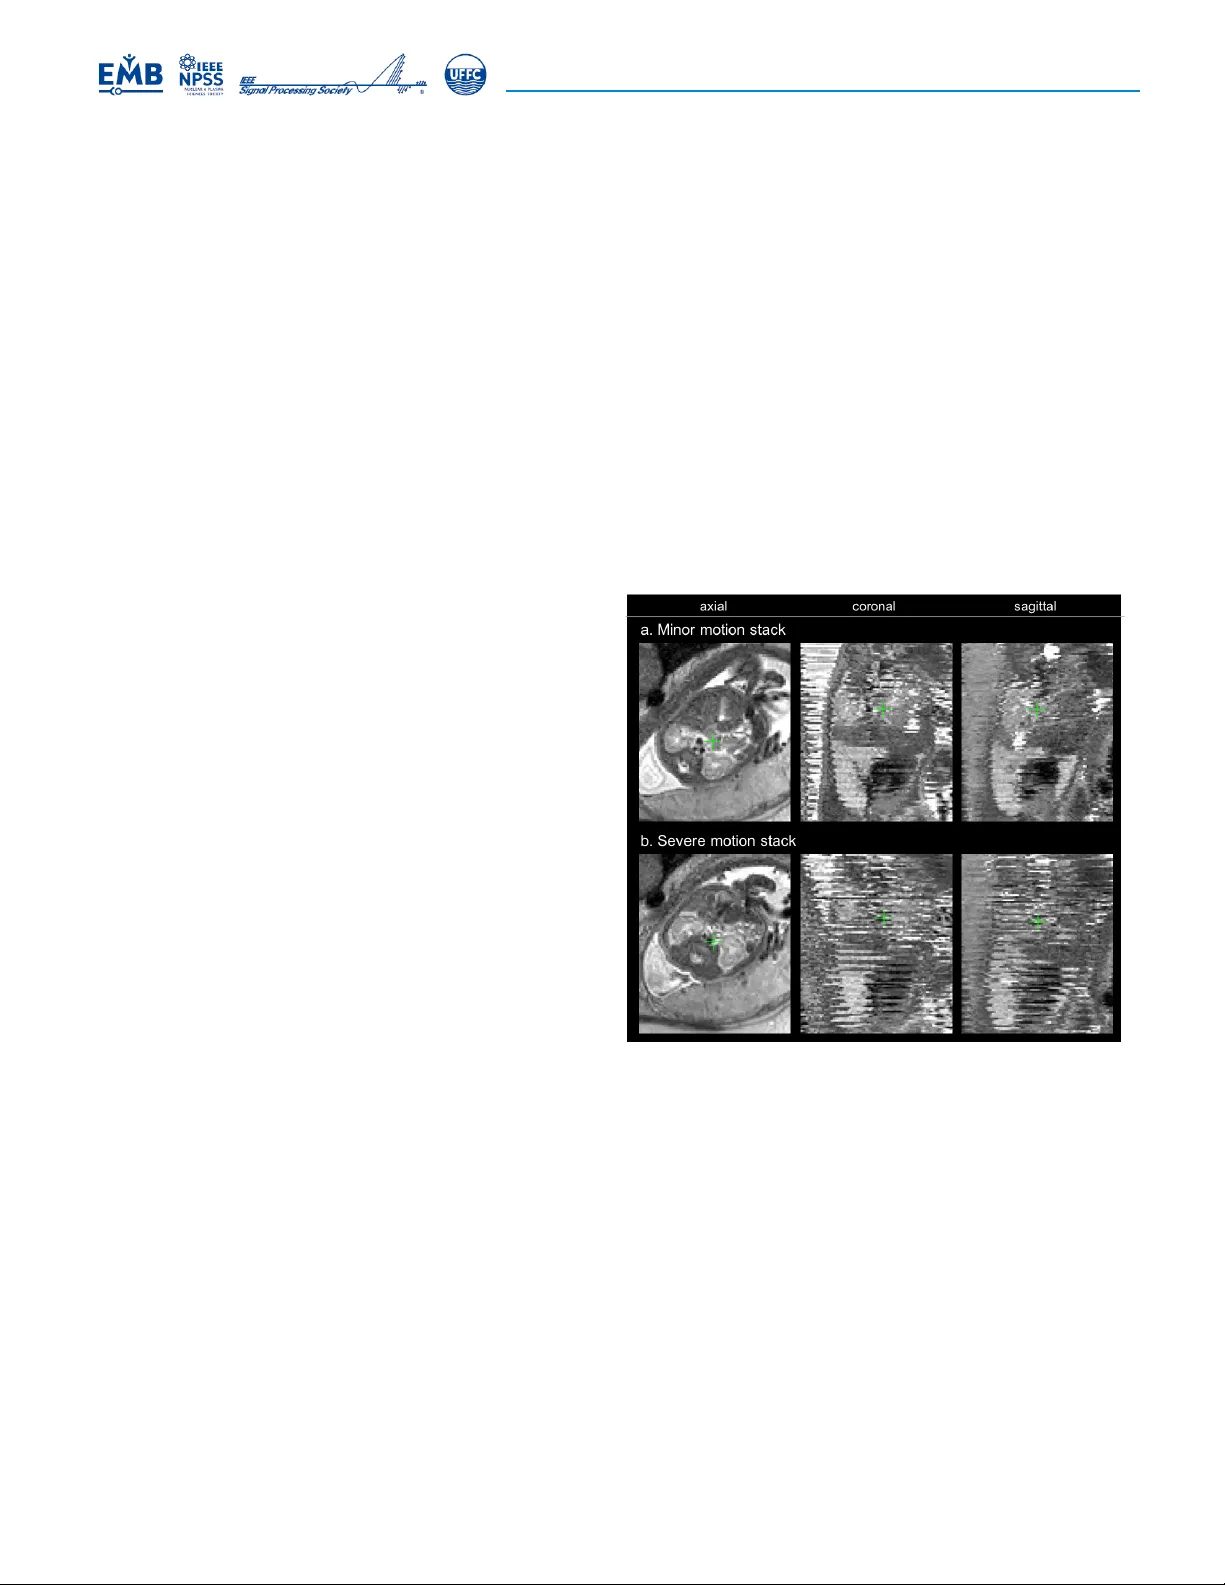

본 논문은 태아 인‑우두 MRI에서 흔히 발생하는 비강직 움직임, 즉 복부와 태반이 호흡·자세 변화에 따라 구부러지거나 늘어나는 현상을 해결하고자 한다. 기존의 슬라이스‑투‑볼륨 등록(SVR) 기법은 슬라이스와 볼륨 사이의 강체 변환만을 추정하기 때문에, 뇌와 같이 거의 강체 움직임만을 보이는 부위에만 적용 가능했다. 그러나 태아 몸통과 태반은 지역적인 비강직 변형이 빈번히 일어나며, 이때 SVR을 그대로 적용하면 재구성된 3D 볼륨이 흐릿해지거나 해부학적 구조가 왜곡된다. 이러한 문제점을 인식한 저자들은 변형 SVR(Deformable SVR, DSVR)이라는 새로운 프레임워크를 제안한다. DSVR은 크게 네 가지 핵심 요소로 구성된다. 첫 번째는 **계층적 전역 변형 보정**이다. 모든 스택을 먼저 3D‑to‑3D 강체 정렬한 뒤, 저해상도 B‑spline 제어점 간격을 사용해 전역적인 비강직 변형을 추정한다. 이 단계에서는 스택 전체를 가우시안 블러링하여 노이즈와 작은 변형을 억제하고, 큰 형태 차이만을 보정한다. 두 번째는 **슬라이스‑투‑볼륨 변형 정합**이다. 여기서는 재구성된 고해상도 볼륨을 각 2D 슬라이스에 맞추는 3D‑to‑2D 정합을 수행한다. 변형 파라미터는 매 DSVR 반복마다 B‑spline 제어점 간격을 점점 좁혀가며 세밀하게 조정한다(계층적 해상도 감소). 이 과정에서 강체 정합을 배제함으로써 초기 단계에서 얻은 전역 변형이 지역 변형을 억제하지 않도록 설계하였다. 세 번째는 **변형된 PSF 모델링**이다. 기존 SVR에서는 변환된 PSF가 회전·이동된 가우시안 형태였지만, DSVR에서는 비강직 변형을 반영해 PSF 자체가 비가우시안 형태로 변형된다. 이를 통해 시뮬레이션된 슬라이스와 실제 슬라이스 사이의 차이를 보다 정확히 모델링한다. 네 번째는 **구조 기반 이상치 제거**이다. 두 단계의 이상치 제거가 적용된다. 전역 이상치는 변환 후 슬라이스와 볼륨 사이의 정규화 상관(NCC)이 사전 정의된 임계값 이하인 경우 해당 슬라이스를 완전히 배제한다. 지역 이상치는 SSIM(구조적 유사도) 지표를 이용해 슬라이스 내부의 저유사도 영역을 가중치 0으로 설정함으로써, 국소적인 오정합이 최종 볼륨에 미치는 영향을 최소화한다. 이러한 가중치는 기존 EM 기반 로버스트 통계에서 사용하던 voxel‑level 확률 대신, NCC·SSIM 기반 이중 가중치로 대체된다. 실험에서는 먼저 시뮬레이션 데이터를 이용해 정량적 평가를 수행하였다. DSVR은 기존 SVR 및 패치‑투‑볼륨(PVR) 대비 평균 SSIM이 0.12~0.18 상승하고, RMSE가 15% 이상 감소하였다. 이어 28‑31주 임신 주수의 20건 임상 데이터에 대해 동일한 정량 지표를 적용했으며, 비강직 변형이 심한 경우에도 DSVR이 뚜렷한 해부학적 구조(척추, 장기 경계 등)를 복원함을 확인했다. 마지막으로 20‑34주 GA 범위의 100건 실제 사례에 대해 정성적으로 평가했으며, 전문가 판독 결과 DSVR 재구성 영상이 기존 방법에 비해 해부학적 세부가 더 선명하고, 진단에 필요한 구조적 정보를 충분히 제공한다는 결론에 도달했다. 본 연구는 비강직 변형이 빈번히 발생하는 태아 몸통·태반 MRI에서 신뢰성 높은 고해상도 3D 재구성을 가능하게 하며, 향후 태아 질환 진단, 성장 평가, 그리고 연구용 데이터베이스 구축에 중요한 전처리 단계로 활용될 수 있다. 또한 계층적 변형 정합과 구조 기반 이상치 제거라는 두 가지 핵심 아이디어는 다른 비강직 변형이 존재하는 의료 영상 분야에도 확장 가능성을 제시한다.